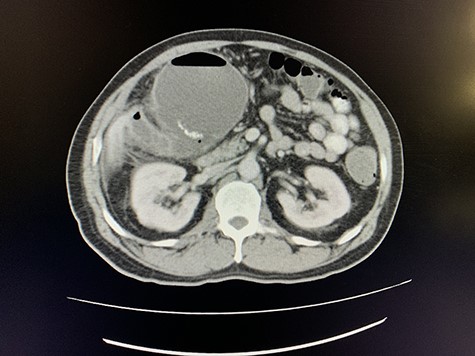

A computed tomography (CT) scan of the abdomen revealed an enlarged, thickened gallbladder with multiple stones, communicating with an intrahepatic collection in segment 4 measuring 116 × 80 mm, with an associated air fluid level and air locules (Fig. 1). There was an apparent fistulous tract to the hepatic flexure of the colon, another large collection in segment 6 (97 × 96 mm) as well as other smaller collections (Figs 2 and 3).

Axial view of portovenous phase of CT scan of the abdomen demonstrating enlarged, thickened gallbladder with radio-opaque gallstones with apparent fistulous communication with the hepatic flexure of the colon with associated pneumobilia.